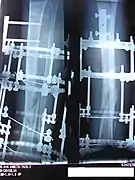

The photographs and radiographs illustrate the application and emplacement of an external fixator, an Ilizarov apparatus, to repair the open fracture of the lower left leg of a man. The photographs were taken four weeks after the patient fractured the shinbone (tibia) and the calfbone (fibula) of his left leg, and two weeks after the surgical emplacement of the Ilizarov apparatus to immobilise the leg and isolate the wound and fracture site to facilitate healing.

X-ray of the fracture site and the emplaced apparatus, two months post-fracture; perspective 1-4.

X-ray of the fracture site and the emplaced apparatus, two months post-fracture; perspective 2-4.

X-ray of the callus forming at the fracture site, three months post-fracture; perspective 3-4.

X-ray of the callus forming around the fracture site, three months post-fracture; perspective 4-4.

X-ray perspectives of the callus-formation progress and healing of the fractured tibia and fibula bones, four months post-fracture.